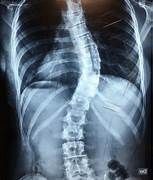

Qué es la escoliosis?

La escoliosis consiste en la pérdida de la alineación normal de la columna en el plano frontal, es decir, cuando miramos a una persona de frente. En ese plano la columna ha de ser prácticamente recta. Cuando se producen curvaturas de la columna hablamos de escoliosis.

Vertebral Body Tethering